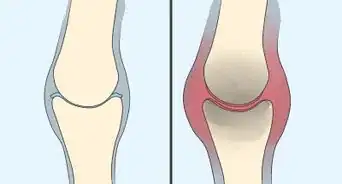

3Take medications for bone loss. There are medications available to slow bone loss and increase bone density.[29] These are usually used after a diagnosis of osteoporosis (bone loss) has been confirmed. Consult a doctor if you think this might be a good option for you.